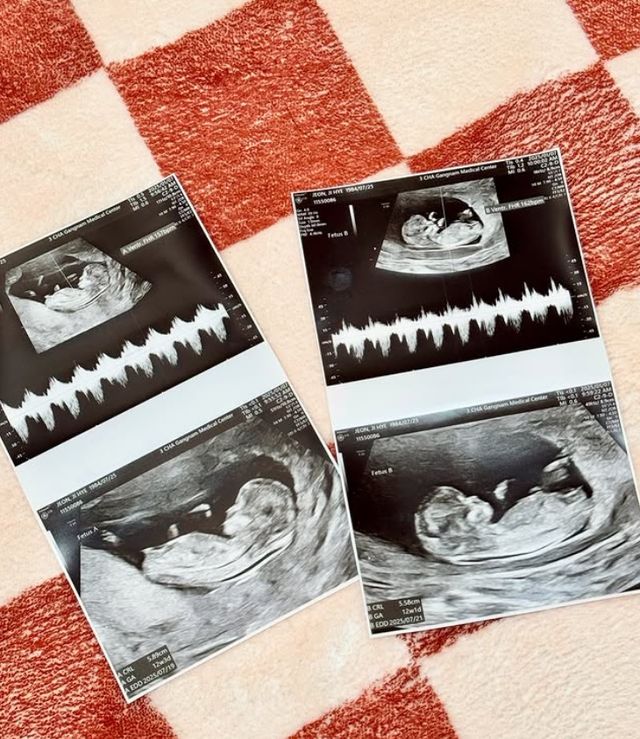

10일 레이디 제인은 "여러분, 저희에게 드디어 소중한 새 생명이 찾아왔답니다♥"라는 글과 함께 초음파 사진을 공개했다.

"게다가 무려 쌍둥이에요"라고 고백한 그는 "처음엔 덜컥 걱정이 앞섰지만 지금은 제 운명을 받아들이고(?) 감사히 잘 품고 있답니다 ㅎㅎ"라는 근황을 전했다.

현재 12주가 지났다는 레이디 제인은 입덧과 붓기가 있다며 "급 약속취소도 양해해 준 지인들에게 다시금 감사 드린다"고 덧붙였다.